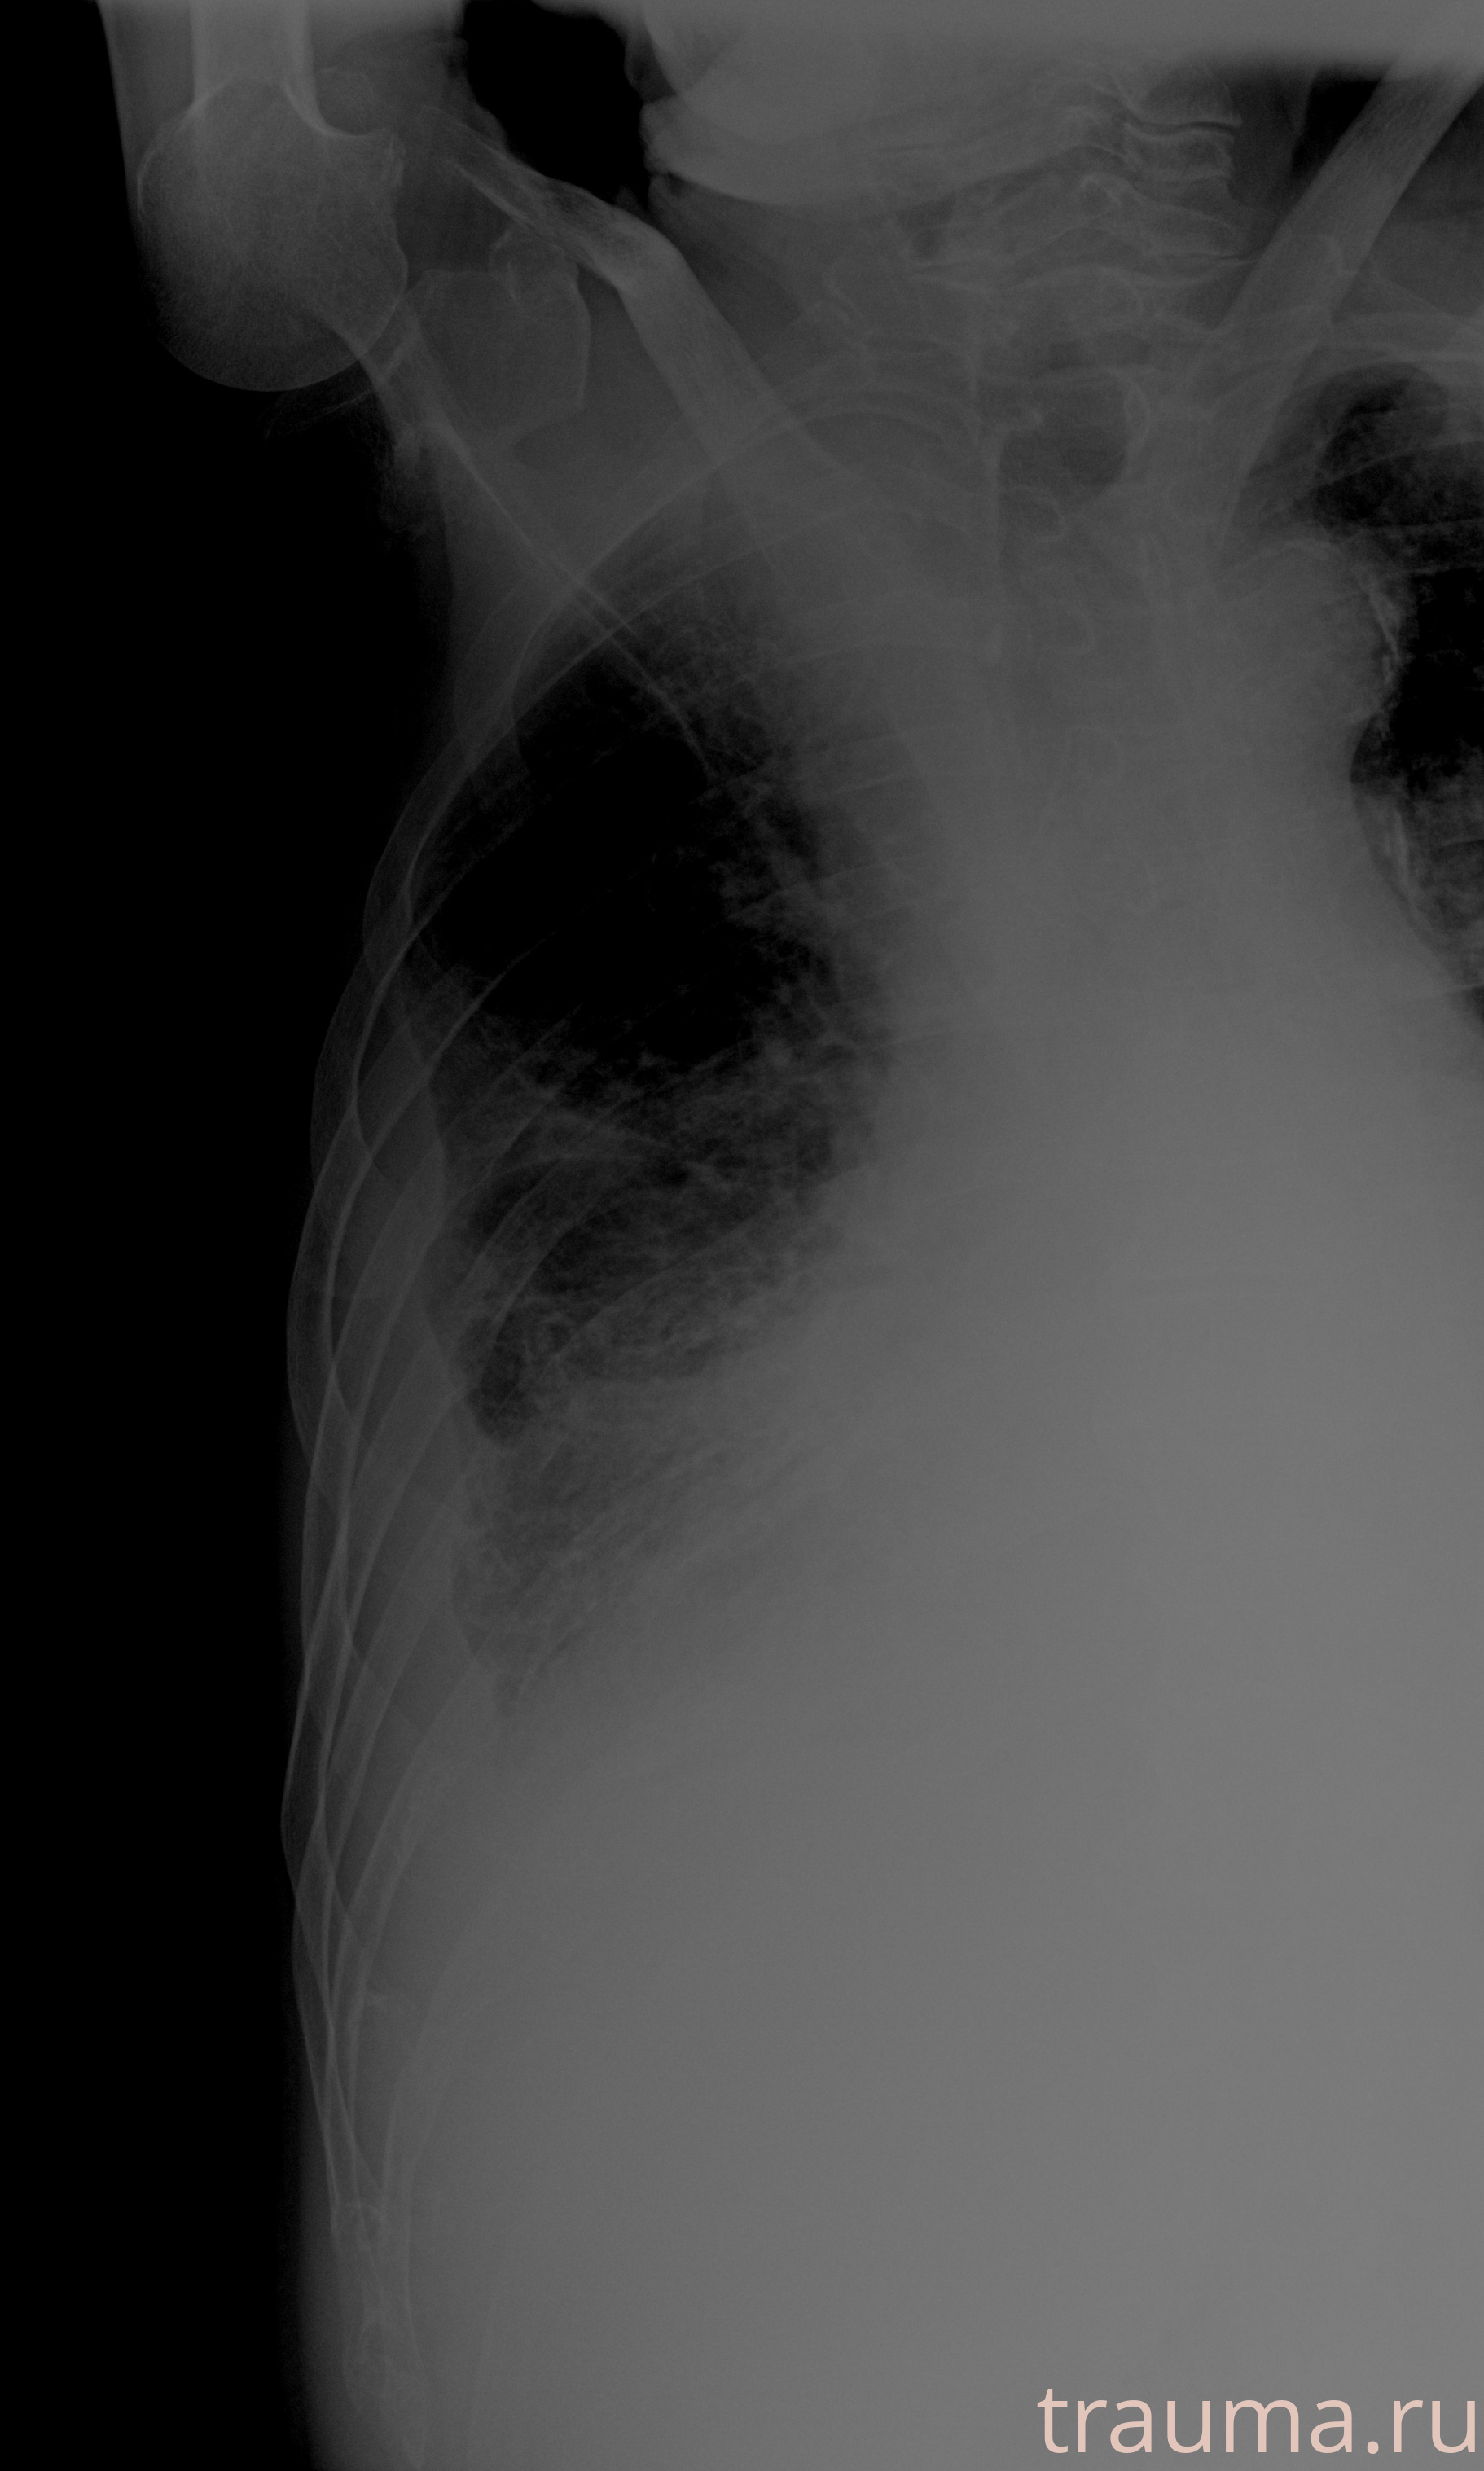

Рентген на дому: по вашему адресу приезжает врач-рентгенолог, травматолог-ортопед с мобильным рентгеновским аппаратом, проводит диагностику травмы или заболевания, делает необходимые рентгенограммы, дает рекомендации по дальнейшему лечению. Получить качественные снимки в домашних условиях возможно благодаря уникальной методике, разработанной МосРентген Центром для института  Склифосовского

при переломе шейки бедра и пневмонии от компании МосРентген Центр - партнера Института имени Склифосовского